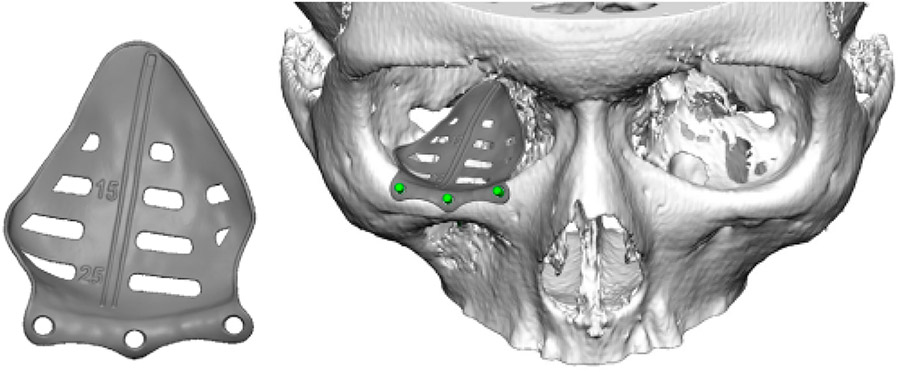

The patient underwent a Caldwell-Luc approach and concurrent orbital floor reconstruction. A one-stage approach was chosen for a faster recovery and single surgery. Correction of enophthalmos and dystopia was performed using a patient-specific CAD/CAM implant (Fig. 3) assisted by intraoperative navigation and CT scan (Fig 4.). The 0.3mm orbital floor titanium plate was placed through a transconjunctival approach (Fig. 5). The patient was found to be complaint free and full recovered at 6th-month follow-up (Fig 1.).